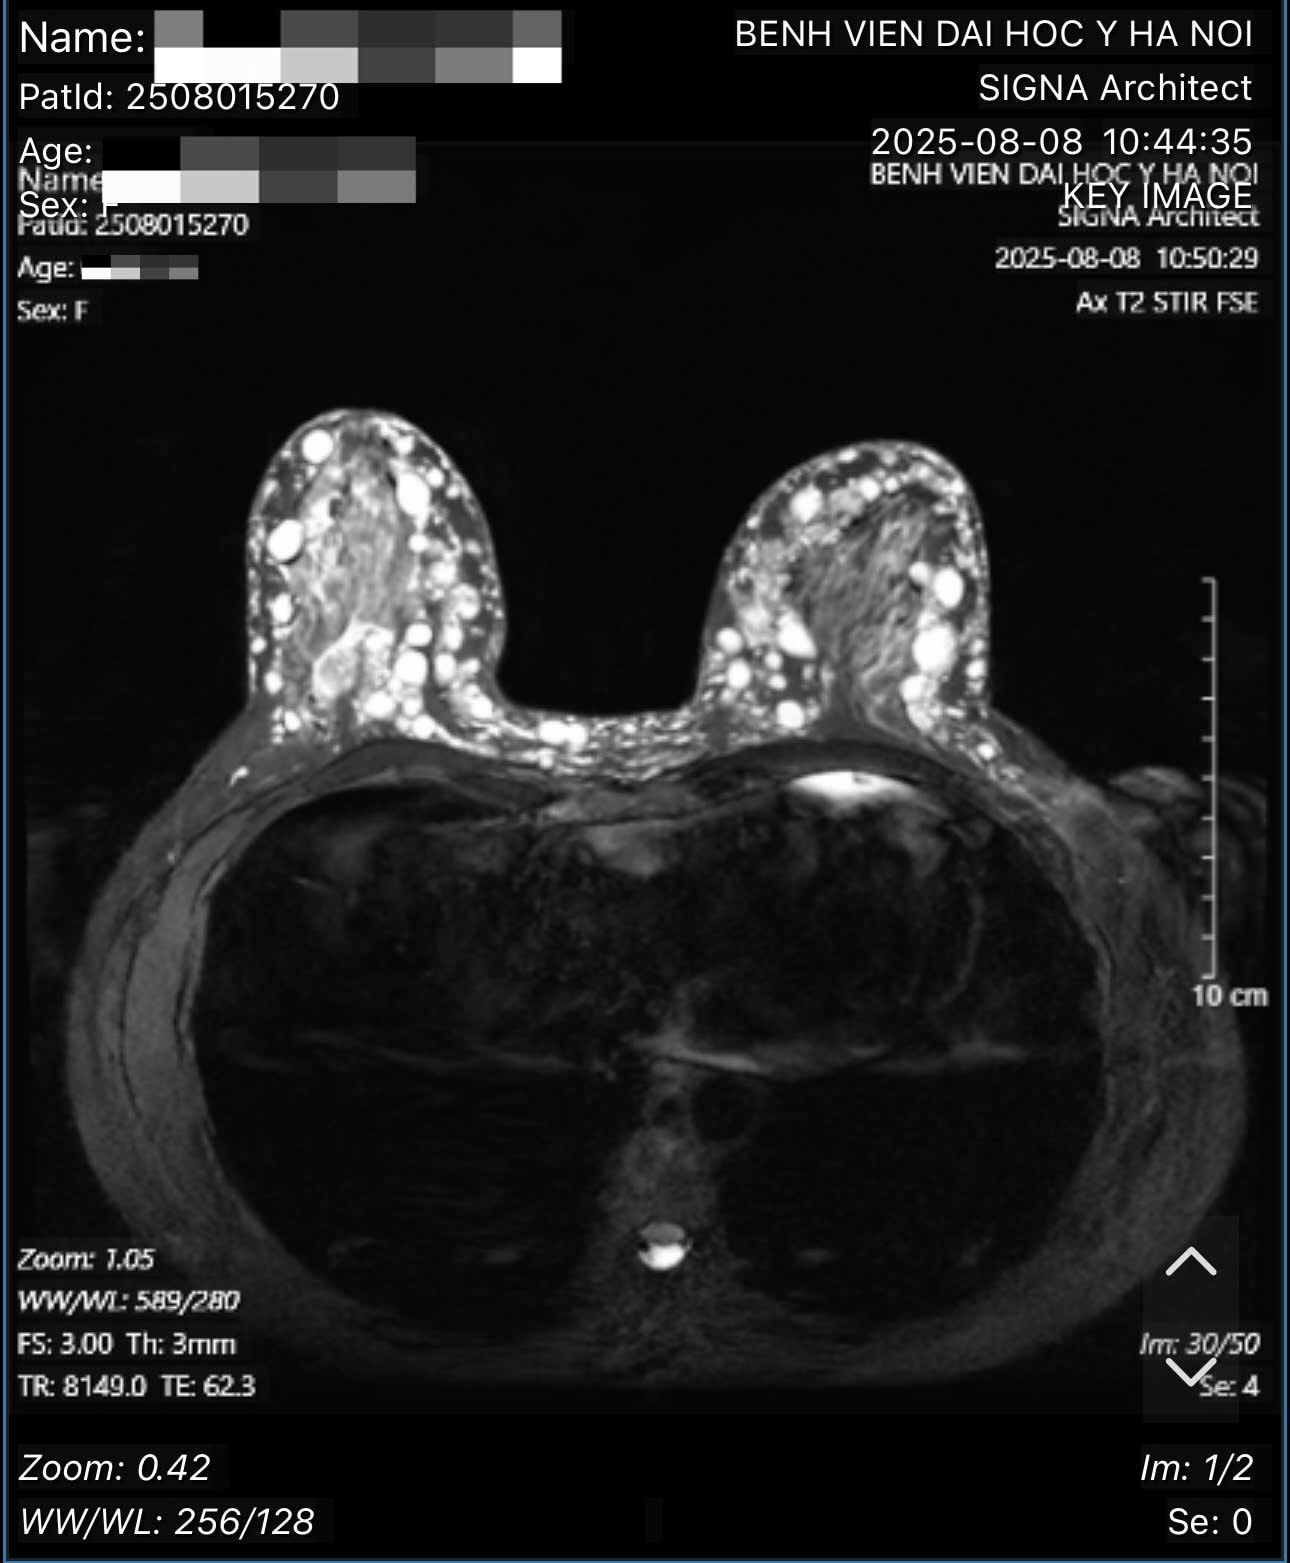

Hình ảnh các hạt sillicone tại ngực bệnh nhân. Ảnh: Bác sĩ cung cấp

Theo bác sĩ Hồng, qua thăm khám, xét nghiệm và các hình ảnh chụp chiếu, bác sĩ xác định bệnh nhân bị u hạt silicon hai bên ngực (hay còn gọi là siliconoma), thâm nhiễm toàn bộ tổ chức tuyến vú hai bên, đến các tổ chức mỡ dưới da, trung bì da, hay sâu đến lớp cân cơ ngực lớn - là biến chứng của việc tiêm silicon lỏng.